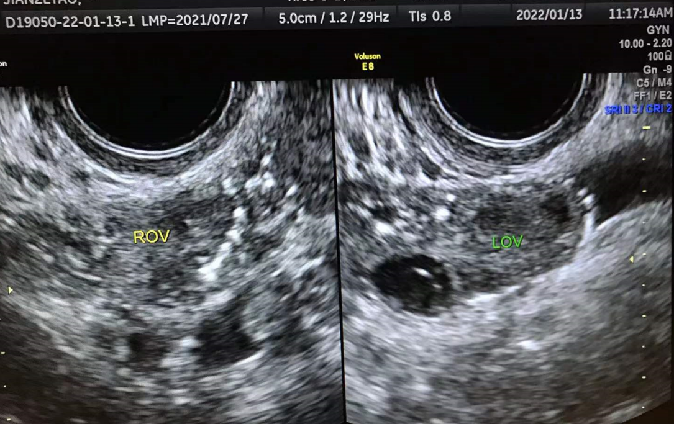

先请看两张女性慢性盆腔炎的超声照片:

左侧卵巢周围串珠样强回声钙化斑

双侧卵巢周围强回声钙化斑

这位女性患盆腔炎多年,一直没有进行过正规的治疗,因不孕症前来就诊,超声检查发现钙给双侧卵巢砌上了“围墙”。